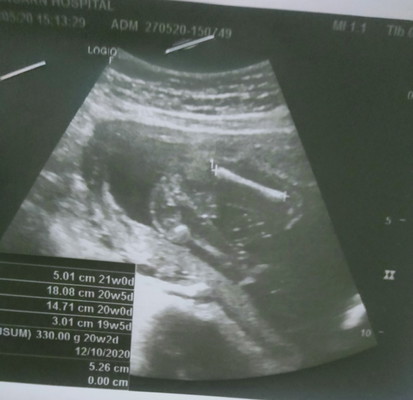

ตั้งครรภ์ได้ครึ่งทางแล้วจ้า20สัปดา

กว่าจะผ่านอะไรมาได้ มันก็เหนื่อยเหมือนกันเนาะ พอได้ไปซาวมองเห็นลูกดิ้น ก็มีกำลังใจขึ้นมา โดยอัตโนมัตเลย ตอนนี้ได้20สัปดาแล้วนับถือใจตัวเองที่ประตับประคองใจตัวเองจนมาถึงทุกวันนี้ได้ จุดคนนินทา จุดครอบครัวรับไม่ได้ จุดที่ทุกคนบอกให้เราไปทำแท้ง แต่เราไม่ไปเราจะสู้ปัญหาไปด้วยกันน่ะ เบบี๋น้อย #คาดว่าเป็นผู้ชายจ้าา